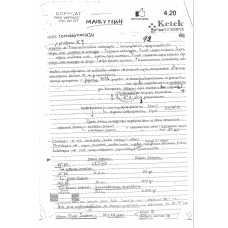

MAIEYTIKH

Σημείωση: Οι παραπάνω φωτογραφίες αποτελούν προεπισκόπηση μέρους των σημειώσεων!

Στην περίπτωση που επιθυμείτε να δείτε ολόκληρες τις σημειώσεις, μπορείτε να περάσετε από το κατάστημα μας.